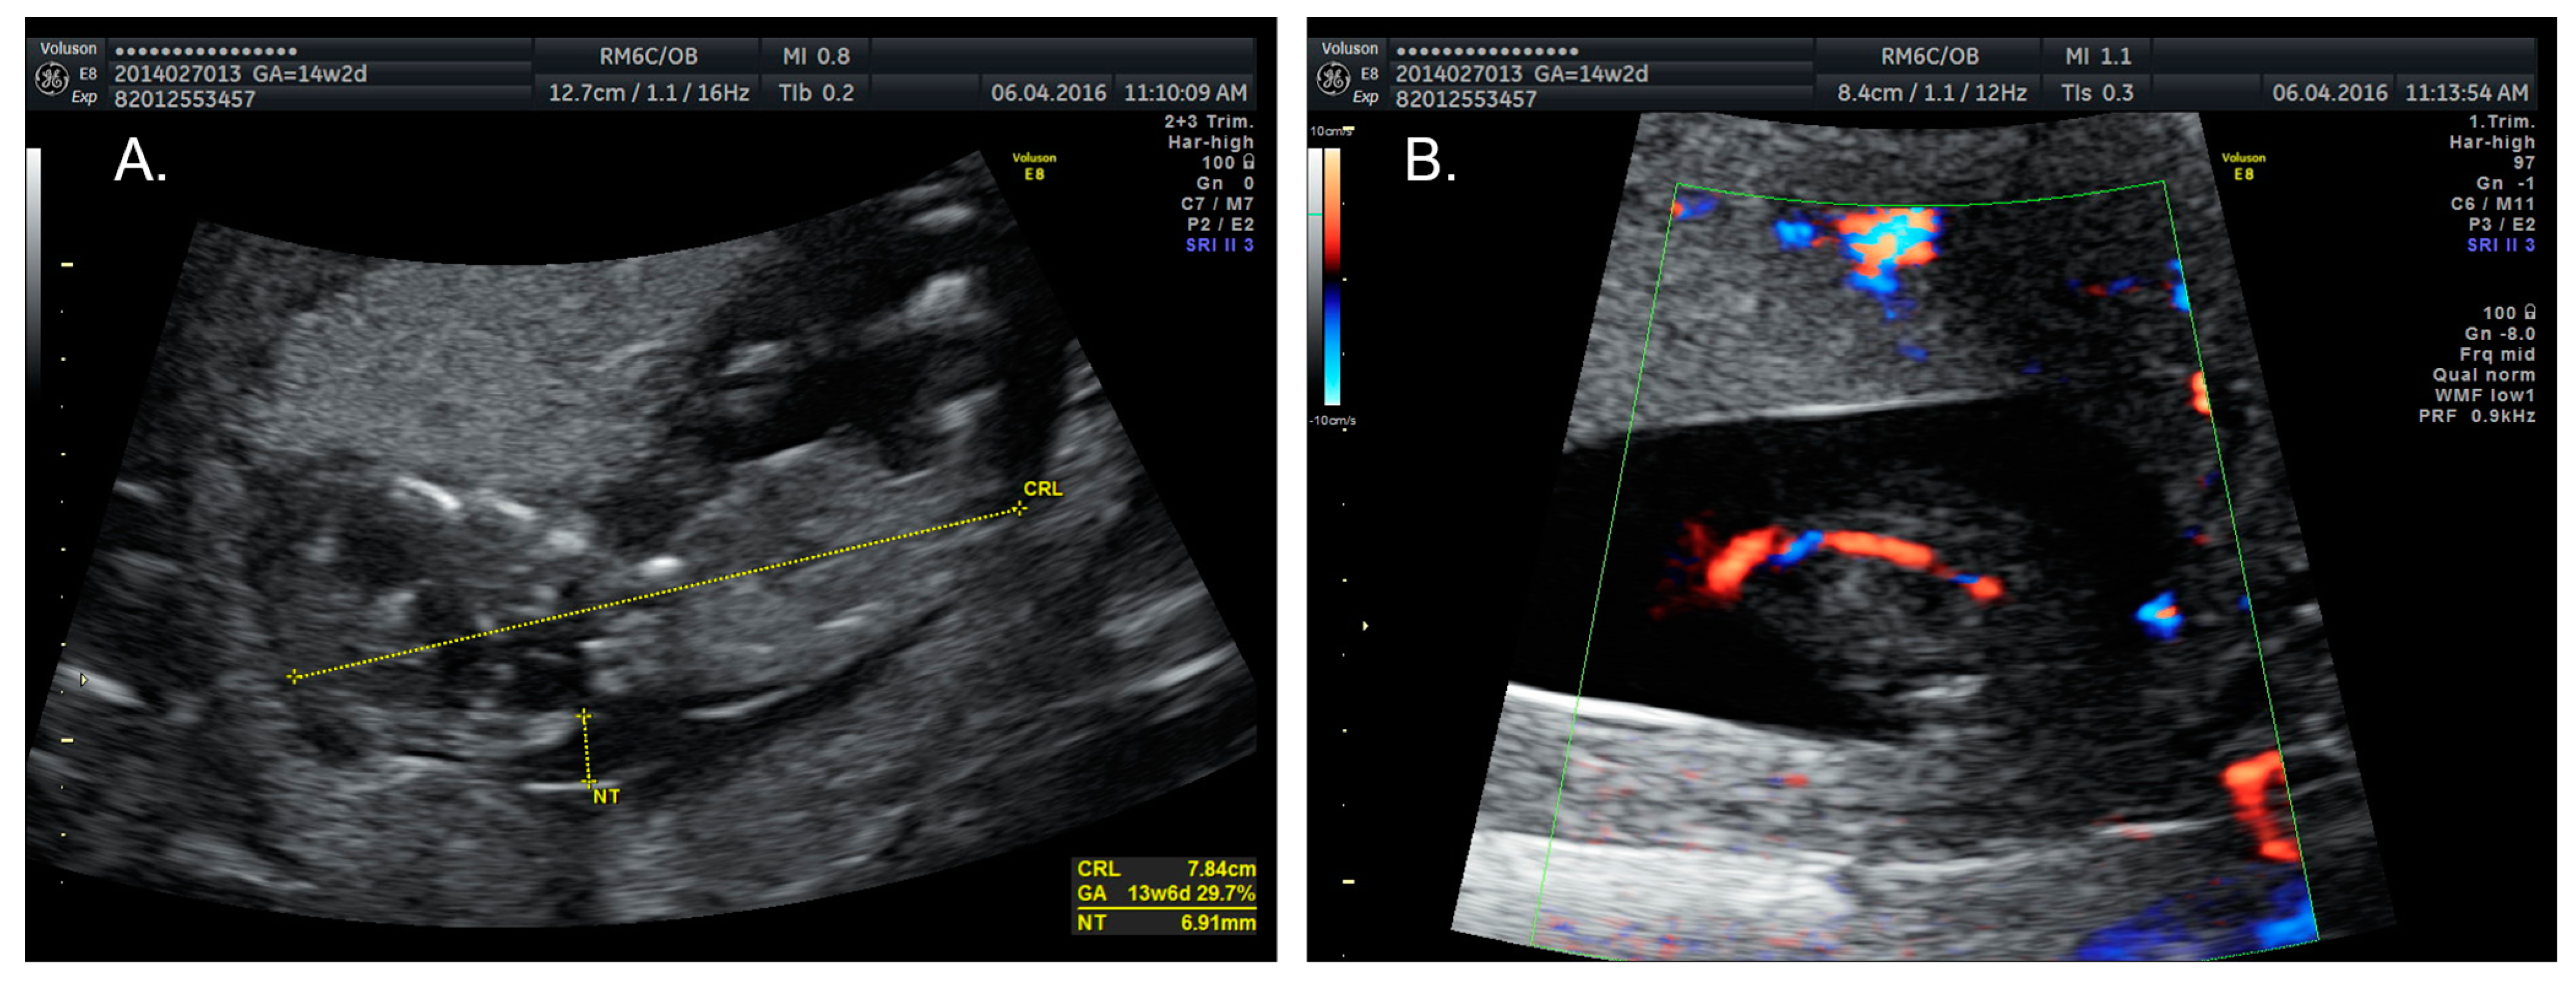

2.1. Case 1

| Increased nuchal translucency (n = 4; 18%) | + | − | [1,3,5,21,23] |